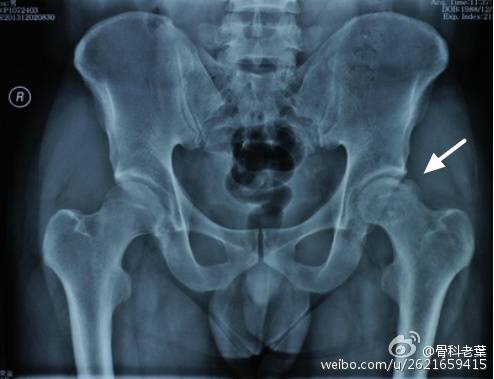

II期 病人有髋部症状,磁共振出现异常,X线片显示股骨头出现透光和硬化改变

III期 磁共振出现异常,X线片显示软骨下塌陷(新月征),股骨头内出现空洞,股骨头没有变扁

II期和III期的患者治疗方法相同,因为此时股骨头虽然还没有变形,暂时还不需要行人工关节置换术,但是股骨头已经出现空洞,随时股骨头就会塌陷变形,所以单纯的股骨头减压术是不能达到治疗效果的。这时就需要在股骨头减压的同时,植入一根支撑棒,顶住股骨头空洞区,防止股骨头在负重的情况下过早塌陷。其他治疗同之前相同,口服以上药物,定期复查,密切观察病情发展,尽量避免重体力劳动和爬山爬楼。

另附典型病例若干: